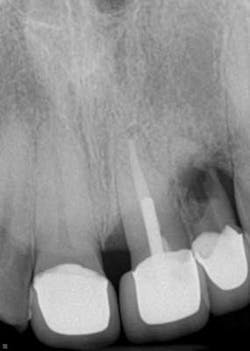

3. Comfortably numb: how dental anesthesia can differentiate your endodontic practice — In today’s economic climate, dentists are looking for ways to differentiate themselves within the community. Here, Dr. Diwakar Kinra shows you how Onset from Onpharma can be used to provide comfortable and profound anesthesia for your endodontic patients as he presents three clinical case studies.